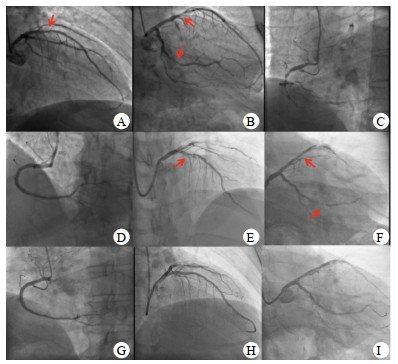

1 资料与方法患者,男性,74岁,因“冠脉介入术后即刻胸闷伴呼吸困难”,于2020年12月29日入急诊监护室。入监护室前经桡动脉行冠脉造影示右冠(right coronary artery, RCA)慢性闭塞病变,左前降支(left anterior descending artery, LAD)近中段狭窄80%,左回旋支(left circumflex artery, LCX)支架内狭窄80%。开通RCA闭塞病变,植入2枚支架(图 1 A~D),手术过程顺利。术后即刻突发胸闷胸痛,呼吸困难,送至监护室,心电图提示前壁V1~V5导联ST段抬高0.4 mV(图 2)。血压105/60 mmHg(1 mmHg=0.133 kPa),心率80次/min,呼吸频率30次/min,氧饱和度88%(空气氧)。考虑急性前壁心肌梗死,立即行急诊冠脉造影,经桡动脉,示LAD中段狭窄80%,但较之前造影未见进展,TIMI Ⅲ级血流;LCX支架处狭窄80%,血流TIMI Ⅲ级;RCA支架通畅,膨胀良好,血流TIMI Ⅲ级(图 1 E~G)。在LAD近中段植入两枚支架,并于LCX支架狭窄处行球囊扩张(图 1 H、I),术中ACT为230~270 s。

| A~D为第一次冠脉造影和治疗:A~C为患者入监护室前第一次行冠脉造影LAD和LCX重度狭窄,RCA闭塞;D为RCA治疗植入支架后血流通畅;E~G为再次胸痛后造影:E~F为患者胸痛后再次急诊冠脉造影LAD及LCX血流通畅,未见血栓,狭窄较前无变化;G为复查RCA造影示支架通畅;H~I为二次治疗后影像:H为LAD支架植入后解除狭窄;I为LCX球囊扩张后解除狭窄 图 1 患者冠脉造影 |